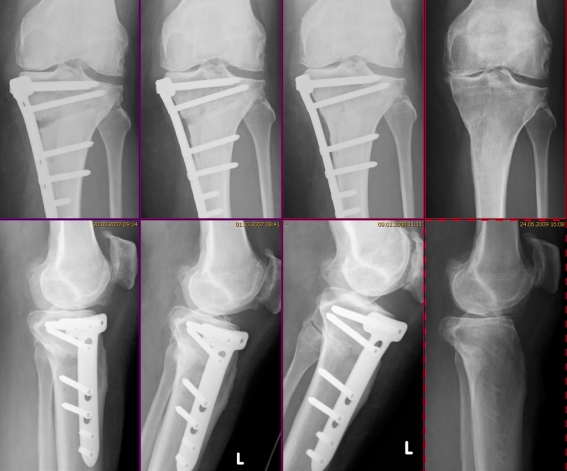

A retrospective study of 53 consecutive cases in which no interposition material was used to fill the wedge, with gap openings between 5 mm and 20 mm (Table 1), showed that ossification of the gap always progressed from the lateral hinge towards the medial side. Standard radiographs showed at least 75% of the gap filled in with new bone within 6−18 months (Figs. 4 and 5). The plate should therefore not be removed before 12−18 months after implantation. Weight bearing up to the point of discomfort was encouraged as early as two days after surgery.

Fig. 4.

Bone-to-bone contact at the osteotomy site without interpositioned graft, as seen on anterior−posterior radiographs (bone growth proceeds from lateral to medial)

Fig. 5.

A typical follow-up showing bone growth without interpositioned graft (53-year-old woman; wedge opening 10 mm, 6 weeks, 3 months, 6 months, 23 months postoperatively)